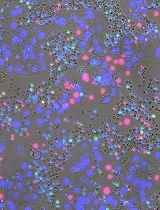

Immunotherapy has demonstrated great therapeutic potential by activating the immune system to fight cancer. However, little is known about the specific dynamics of interactions that occur between tumor and immune cells. In this protocol we describe a novel method to visualize the interaction of tumor and immune cells in the lung of live mice, which can be applied to other organs. In this protocol fluorescent-labeled tumor cells are transferred to recipient mice expressing fluorescently tagged immune cells. Tumor-immune cell interactions in the lung are then imaged by confocal or two photon microscopy. Analysis of tumor interactions with immune cells using this protocol should aid in a better understanding of the importance of these interactions and their role in developing immunotherapies.

A number of immunotherapies have demonstrated great promise in treating cancer. Understanding the spatial temporal resolution of how these tumor-immune interactions occur is important for enhancing and developing new immunotherapies. In this protocol we describe a novel method to directly visualize tumor-immune cell interactions in vivo in mouse lung. This protocol is initially described in our work examining the interactions of patrolling monocytes and tumor cells in the mouse lung (Hanna et al., 2015). This fluorescent microscopy protocol uses the vacuum imaging ring to stabilize and image the lung, which was initially described by Looney and colleagues (Thornton et al., 2012). In this protocol fluorescent-labeled tumor cells are transferred to recipient mice expressing fluorescently tagged immune cells. Tumor-immune cell interactions in the lung are then imaged by confocal or two photon fluorescent microscopy using the vacuum imaging ring. This protocol allows for the addition of other immune cell markers by intravenous (IV) injection of fluorescently labeled antibodies, and is adaptable to image tumor-immune cell interactions in other organs. Quantitative information such as the localization, engulfment of tumor material, timing, speed and frequency of these immune cell interactions can be collected using this protocol. This protocol should aid in helping to better understand the specific immune-tumor cell interactions that are important to developing better immunotherapies in the future.